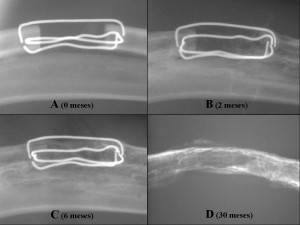

Tanto en los estudios con técnicas de diagnóstico por la imagen (Rx, TC, RM) como de microscopía óptica y electrónica, en los defectos rodeados de aloinjerto aórtico criopreservado (grupo arteria) se observó un progresivo aumento de densidad a nivel del defecto, llegando a restablecerse por completo la continuidad del radio, con un patrón córtico-medular similar al del hueso normal.

Además se observó que la regeneración de hueso se producía dentro de los límites de la arteria, con imágenes sugerentes de un proceso de osificación endocondral, con una capa cortical homogénea y progresivamente más gruesa según el tiempo transcurrido desde la intervención que se adaptaba estrechamente a los límites y contornos de la pared arterial y con un espacio medular ocupado por tejido hematopoiético.

(A), 2 meses (B), 6 meses (C) y 30 meses (D) con regeneración ósea completa